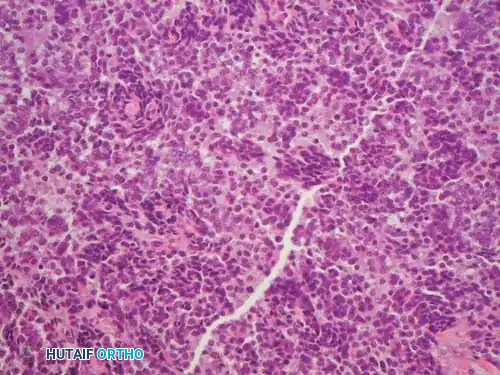

Fig. 22-9 A and B, Anteroposterior and lateral radiographs of the left fibula of a 7-year-old girl with Ewing sarcoma. Involvement of a large portion of the bone (or even the entire bone) is typical of Ewing sarcoma. C, MRI shows a large soft-tissue mass. D, Typical microscopic appearance of Ewing sarcoma.

Histologically, Ewing sarcoma is the quintessential "small round blue cell tumor." The microscopic architecture consists of dense sheets of uniform, small, round cells with scant cytoplasm and very little intercellular matrix.

Because the light microscopic appearance is highly nonspecific, advanced cytogenetic and immunohistochemical (IHC) studies are absolute requirements to differentiate Ewing sarcoma from other small blue cell tumors of childhood (e.g., lymphoma, neuroblastoma, embryonal rhabdomyosarcoma).